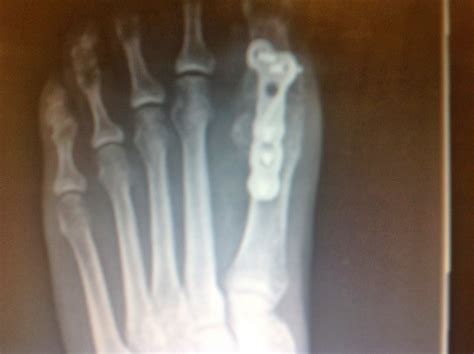

A cast (or even surgery) may be needed if the big toe is broken, a fracture involves a joint, or a lot of small toe fractures occur at once. A broken toe can be painful, but you do not usually need to go to hospital. You think you have broken your big toe. This can cause anything from bruising to an actual break, both of. Big toe joint, hammer toe & bunionette problems do you have a broken big toe? The answer to this question is the ability of an individual to walk with a broken big toe depends on the type of the fracture. Each toe is made up of several bones. Each time the bone heals the tiny breaks, it produces more and more bone until finally you have a piece of bone sticking out where it should not be. Why there is the pain in my big toe? Red or black toenail picture & photo gallery: Big toe joint pain could also be a symptom of an inflammatory disease, such as gout or rheumatoid arthritis. In case of a nondisplaced fracture of the big toe, the individual will be able to walk some distances but it will tend to cause significant pain. Sometimes, a broken toe may become infected or increase the risk of osteoarthritis in that toe in the future.

Your big toe joint pain stock images are ready. A cast (or even surgery) may be needed if the big toe is broken, a fracture involves a joint, or a lot of small toe fractures occur at once. In case of a nondisplaced fracture of the big toe, the individual will be able to walk some distances but it will tend to cause significant pain. However, a very bad fracture or a fracture that goes into a joint is at risk for developing arthritis, pain. One or more of these bones may be fractured after an injury to the foot or toes.

Big toe joint arthritis (hallux rigidus) causes, symptoms, risk factors and treatment options from orthopedic foot & ankle surgeon, stuart katchis, m.d. If this is mismanaged, you could end up with a premature arthritic joint or an inability to walk normally, dr breaking your big toe—which has a lot to do with your balance, strength, and gait—is a more. Big toe joint pain could also be a symptom of an inflammatory disease, such as gout or rheumatoid arthritis. We go over the signs & symptoms, the 100% best treatment options including big toe taping, air casts and recovery time! Healing oils broken toe burns treatment essentail oils essential oils health doterra oils essential oil remedy diy natural products essential oil treatments. It is commonly associated with past trauma in the articulation of the big toe (a broken joint or a ligament sprain), but it is also prevalent in older and overweight people. However, a very bad fracture or a fracture that goes into a joint is at risk for developing arthritis, pain. Watch the video to find out!want to find out what you can do to heal a broken toe fast? The big toe is continually bending up and down as we walk making it prone to wear and tear. Should i take some time off, cross train, and allow my foot to heal, or is it safe to continue running? A description of big toe joint pain due to hallux limitus and surgical treatment including before and after pictures of hallux limitus surgery. Broken toe treatment depends on which toe you have injured and how badly. Most people break a toe by stubbing it or dropping something on it, according to the mayo clinic.

Big toe joint pain could also be a symptom of an inflammatory disease, such as gout or rheumatoid arthritis. A cast (or even surgery) may be needed if the big toe is broken, a fracture involves a joint, or a lot of small toe fractures occur at once. I've been able to keep running on it, though it is painful. Seek broken toe nhs treatment if your toe has suffered an open fracture, if it is bleeding, or has an odd sensation such as pins and needles or numbness. A description of big toe joint pain due to hallux limitus and surgical treatment including before and after pictures of hallux limitus surgery. Out of the five toes (also known as digits of the feet) the pinky toe is the most commonly broken toe with the the big toe, however, is made up of only two bones and one joint. Broken big toe (likewise called acute fractures) are caused by a direct blow or impact, such as seriously stubbing your toe. Each toe is made up of several bones. Should i take some time off, cross train, and allow my foot to heal, or is it safe to continue running? Signs and symptoms are pain, swelling, redness, bruising, and difficulty walking due to the pain (especially with a broken big toe). Big toe joint, hammer toe & bunionette problems do you have a broken big toe? Broken toe face and body healing toes broken bone fractured toe fitness beauty pinky toe toe injuries. However, a very bad fracture or a fracture that goes into a joint is at risk for developing arthritis, pain.